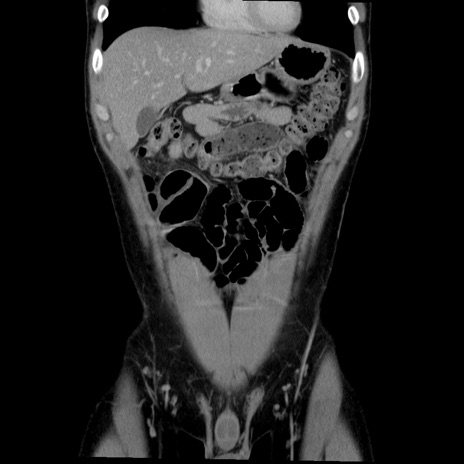

横断像

【症例】20歳代 男性

【主訴】心窩部痛

【現病歴】今朝より上腹部痛あり。一旦軽快していたが再度出現したため救急要請。昨日夕に白身の魚を含む刺身を食べた。

【身体所見】BP 136/89mmHg、HR 74/min、BT 37.0℃、腹部:膨満、軟、心窩部に圧痛あり。反跳痛なし、筋性防御なし、腸雑音やや亢進あり。

【データ】WBC 17700、CRP 0.48